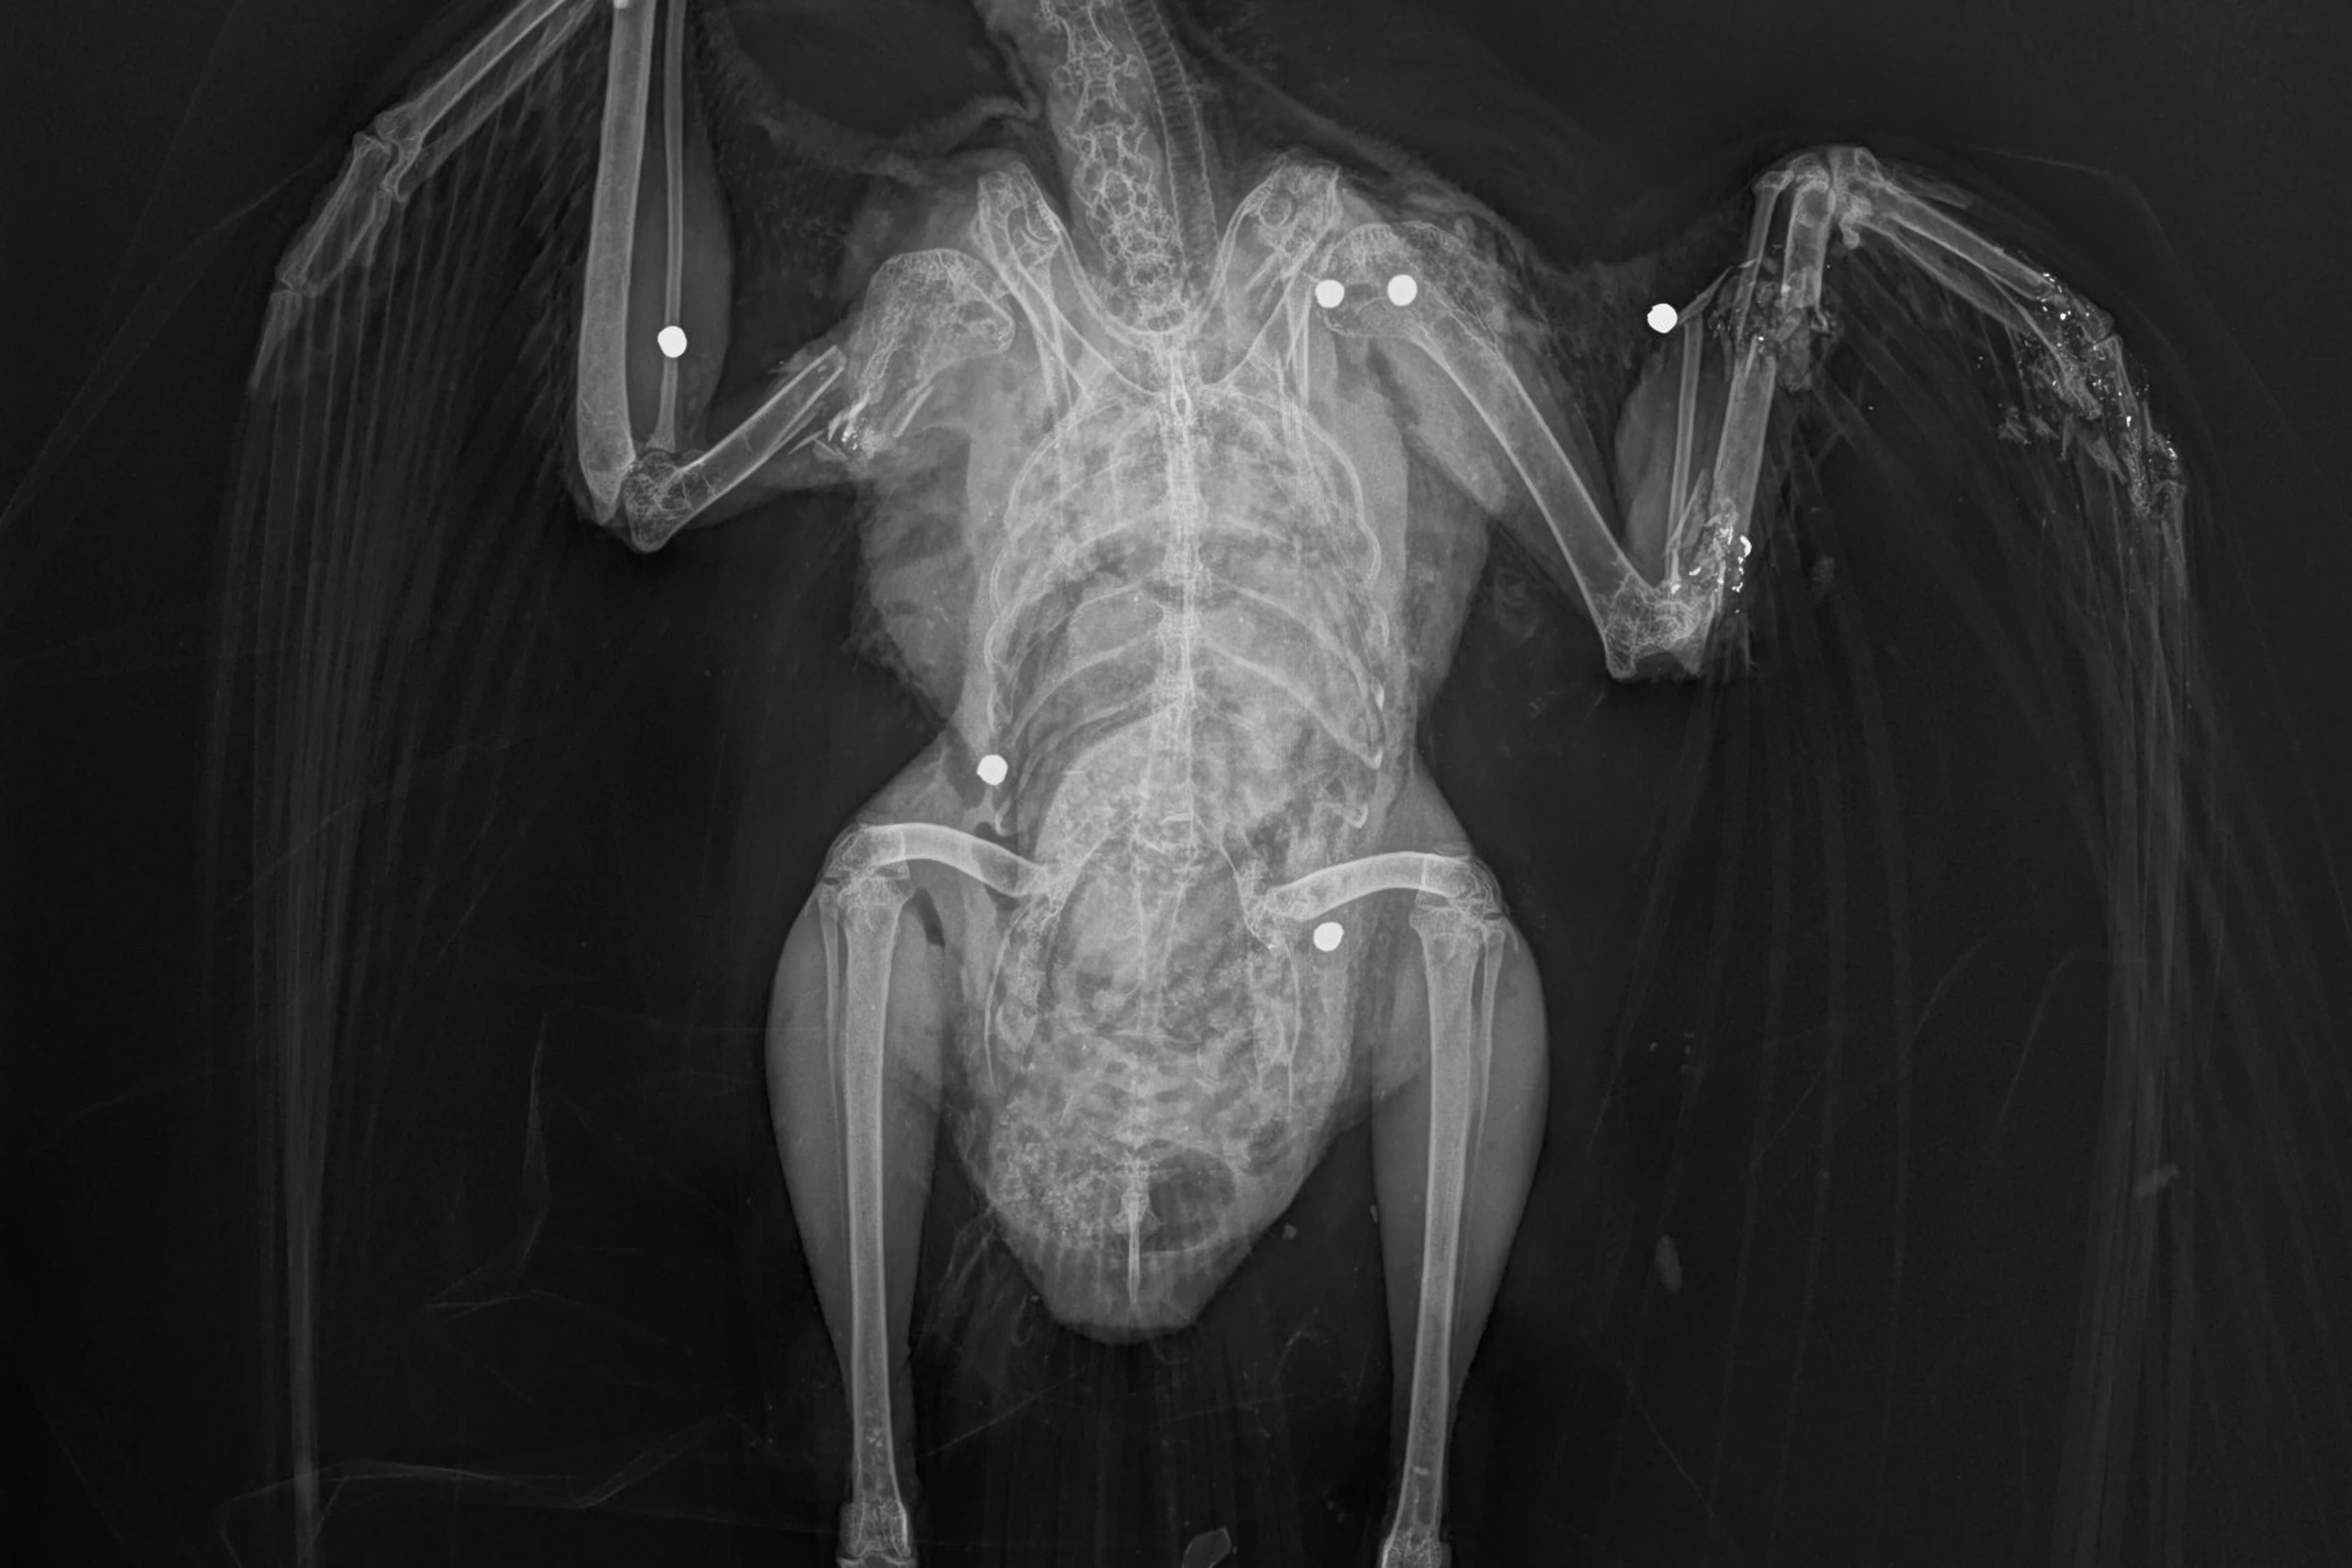

Schussmarken: Typische Verletzungen des Gefieders von Vögeln, die durch Beschuss (meist mit Schrotmunition) entstehen. Wie Sie Schussmarken richtig erkennen und melden können, erfahren Sie hier.

Verletzte Tiere: Benötigen sofortige tierärztliche Versorgung. Wir versuchen nach Möglichkeit zu vermitteln, können aber verletzte Tiere nicht selbst übernehmen. Im Notfall kontaktieren Sie bitte, falls Ihnen bekannt, eine Tierarztpraxis mit Wildtier-Kompetenz oder eine Wildtierstation. Vorrangig ist die Versorgung, die Ursache sollte dabei aber so gut wie möglich dokumentiert werden (Befunde, Röntgenbilder).